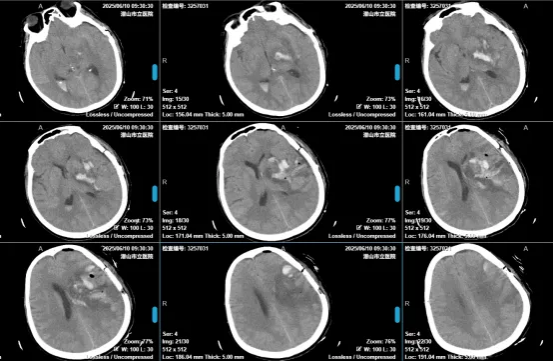

在神經(jīng)外科團隊及ICU、麻醉科、手術(shù)室、輸血科等科室的配合下,芮品和主任及彭承熠醫(yī)生順利為患者實施手術(shù),術(shù)畢即刻復(fù)查CT片見血腫基本清除。